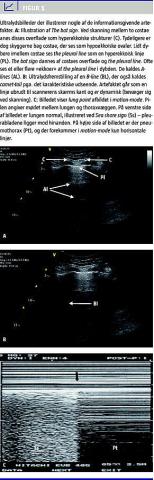

UL-billedet bliver - groft sagt - dannet ud fra refleksioner af lydpulse udsendt fra en transducer. Typisk præsenteres UL-signalerne som et todimensionelt gråtonebillede i B-mode , hvor UL-bølger udsendes i tynd stråle, der reflekteres/absorberes/refrakteres/transmitteres afhængig af vævets ekkogenicitet. Der dannes således et tværsnit af den undersøgte struktur, hvor et punkt afbilledet på UL-apparatets skærm er bestemt af afstanden fra proben og strukturens ekkogenicitet. Brightness (B)-mode kombineres med motion (M)-mode , hvor B-mode gengives som en funktion af tiden, se Figur 1 . Strukturerne kan fremstå isoekkoiske (som leveren), hyper-(lyse) eller hypoekkoiske (mørke). Den benyttede transducerfrekvens bør ligge i et område, der både muliggør overfladisk og relativ dyb skanning dvs. omkring fem MHz. Transduceren, som anvendes til lungeskanning, bør være af liniær eller kurvet type. Nyere scannere kan have filtre aktiveret, der »uheldigvis« kan fjerne nogle af de artefakter, der er informationsgivende [4].

Billedfortolkning ved lungeultralyd

Lungeultralyd starter normalt i zone 1 mellem costa 2 og 3. Først visualiseres de øvre og nedre ribben som kaster hypoekkoiske skygger (Figur) og mellem to ribben ses (hos voksne) 0,5 cm under kostalinien en hyperekkoisk, horisontal linie [4]. Det er the pleural line , der repræsenterer pleura, altså mødet mellem thoraxvæggen og den luftfyldte lunges overflade. Det kaldes the bat sign - de to ribben og pleura danner udseendet af en flagermus i flugt. Fremstillingen af the bat sign bør altid starte enhver lungeultralydundersøgelse, idet det sikrer et korrekt »vindue« med valide informationsgivende artefakter [3, 4].

Nogle af de forskellige informationsgivende tegn i basal lungeultralyd fremgår af Figur 1. For det første ses i den normale lunge lung sliding . Det er et dynamisk tegn, der indikerer pleurabladenes naturlige bevægelse i forhold til hinanden under respirationsbevægelser. Lung sliding bliver tydelig, jo mere man opsøger de kaudale dele af lungen. Lung sliding kan være mere eller mindre udtalt, men giver altid samme vigtige information - de to pleurablade ligger opad hinanden. For at erkende meget små bevægelser kan man supplere med M-mode , hvor man under normale forhold vil opnå et karakteristisk mønster i to dele. Pleural line adskiller to områder som en klar horisontal linje; et område med horisontale linjer øverst på skærmen og nederst et grumset (bølget) område. Et samlet billede, der ligner en kystlinie, deraf tilnavnet Sea Shore Sign , er en alternativ fremstilling af lung sliding . Fravær af lung sliding tyder på PTX, men kan ses ved enhver tilstand med ophævet lungeudfoldelse (massiv atelektase, adhærent pleura, emfysem, simpel apnø og hurtig, overfladisk respiration), og fravær bør derfor kombineres med patientens klinik i øvrigt.

Af ovenstående fremgår det, at en stor del af de pleurapulmonale informationer, som kan opnås med UL, hidrører fra, »hvad man normalt opfatter som UL-artefakter«. Det må i den forbindelse ikke glemmes, at konventionel billeddannelse naturligvis stadig har sin berettigelse især til evaluering af lungekonsolidering og pleuraansamling. Lungekonsolidering er udtrykket for alveolens tab af luft og opfyldning med væske i stedet, som det ses ved pneumoni og atelektase, hvilket altid vil forbedre de akustiske forhold. Konsolideringerne findes gerne basalt og/eller i kontakt med thoraxvæggen, som er en betingelse for brug af UL til diagnostikken. Lungekonsolideringen ligner levervæv i udseende (Figur 2 ). Der kan indimellem ses hyperekkoiske punkter eller linjer, der gengiver luftfyldte områder i bronkier/bronkioler kaldet air bronchograms . Afhængigt af, om de bevæger sig i forhold til respirationen, kan man afgøre, om det drejer sig om ateletatisk væv eller pneumonisk væv. Tilstedeværelse af tumor, malign proces og absces kan ses direkte.

Ultralyd er andre teknikker overlegen i bedømmelsen af pleuraekssudat/-ansamlinger(Figur 2).

Taksigelser: Vi ønsker at takke Daniel A. Lichtenstein, Paris, for lån af billedet i Figur 1C.